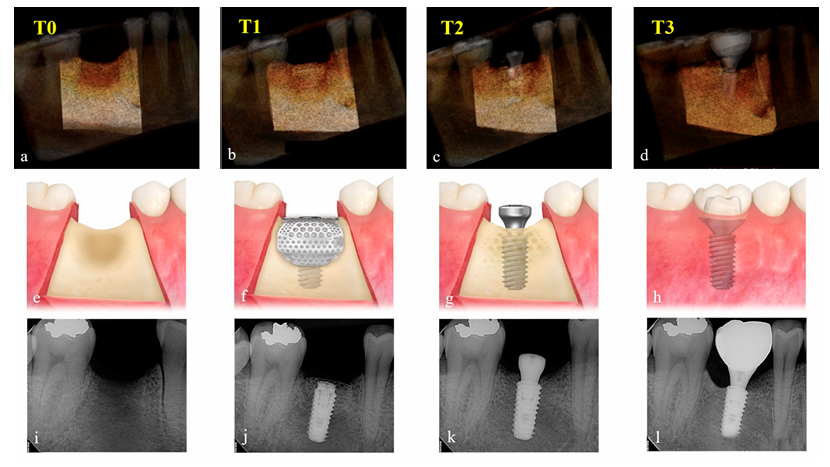

Valutazione del Volume Innestato

Le variazioni nel volume aumentato del materiale di innesto sono state valutate confrontando i dati CBCT ottenuti preoperatoriamente (T0), immediatamente dopo l'intervento chirurgico per l'impianto e GBR (T1), dopo l'intervento di re-entry (T2) e dopo la consegna della restaurazione finale (T3). I parametri di esposizione per la scansione CBCT (campo visivo 35 × 50 mm; dimensione del voxel 0.2 mm; tempo 10.8 s; kV 75; mA 10; prodotto dose area 240 mGy·cm2) sono stati impostati il più bassi possibile (ALARA). Utilizzando il software Aquarium iNtuition (TeraRecon, Durham, NC, USA), il sito dell'impianto è stato ricostruito in un'immagine tridimensionale e segmentato come una regione di interesse (ROI) utilizzando strutture anatomiche vicine, come denti adiacenti, pavimento del seno e canale alveolare inferiore. I compartimenti, che sono radiologicamente uniformi in densità e dimensione, come il corpo dell'impianto e l'abutment di guarigione, sono stati sottratti e il volume (cc) nella ROI è stato calcolato in base ai periodi di tempo (Figura 4) da un esaminatore indipendente e cieco (K.-G.H.). Poiché questo software è ampiamente utilizzato nel campo medico per rilevare con precisione la porzione occlusa dei principali vasi e misurare accuratamente il volume dell'organo per il trapianto, è stato applicato per questo studio per misurare il volume della ROI per integrare la tecnologia CT.

In entrambi i gruppi, il volume innestato, che ha raggiunto il picco di 1.70 ± 0.50 cc nel gruppo Bio-Oss e 1.94 ± 0.26 cc nel gruppo A-Oss a T1, ha continuato a ridursi fino a T3. I volumi innestati sono scesi a 1.17 ± 0.38 cc nel gruppo Bio-Oss e 1.46 ± 0.14 cc nel gruppo A-Oss a T2 e 0.92 ± 0.37 cc nel gruppo Bio-Oss e 1.15 ± 0.16 cc nel gruppo A-Oss a T3; c'era una differenza significativa nei volumi innestati tra i periodi di tempo (p < 0.001, Tabella 3). Tuttavia, non c'era alcuna differenza significativa tra i due gruppi in tutti i periodi di tempo (p > 0.05, Figura 5). Inoltre, non c'era alcuna differenza significativa nelle densità dell'osso rigenerato a T3 tra i gruppi (p > 0.05).